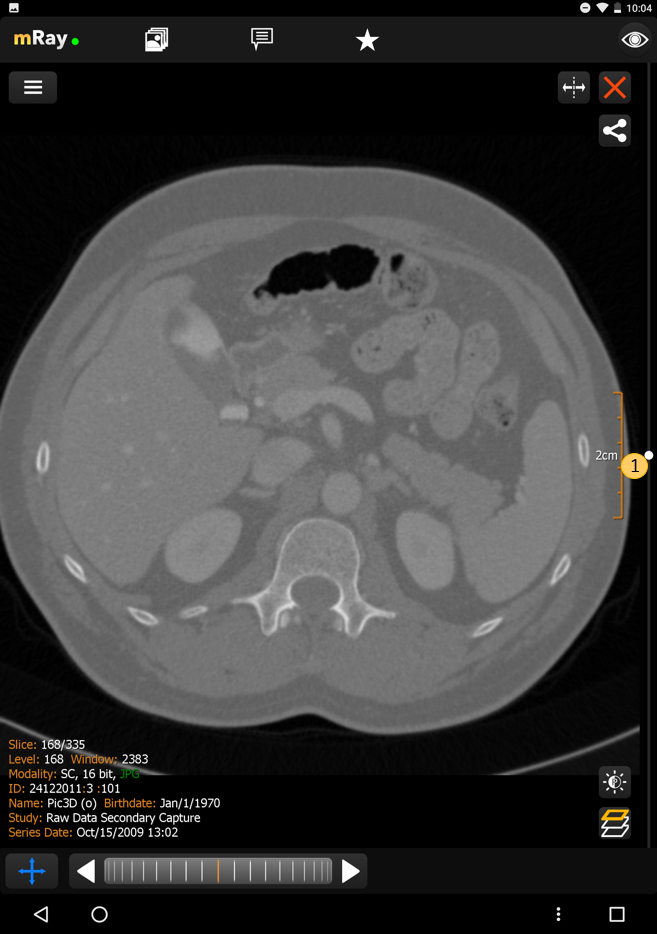

10.4. MPR-Ansichten

Die MPR-Bildlaufleiste erlaubt es Ihnen, mehrere Ansichten gleichzeitig zu öffnen (MPR-Ansichten). Der folgende Screenshot zeigt die MPR-Bildlaufleiste:

Der Screenshot zeigt die MPR-Bildlaufleiste eines MRTs von einem Fuß, die lokal berechnete Rekonstruktion (MPRs) und Informationen zum angezeigten Datensatz.

Sie können die Perspektive mit dem "MPR-Perspektive"-Button (Punkt 2) verändern. Diese Funktion erlaubt es, zwischen Axial, Sagittal und Coronal zu wechseln. Der Button in der rechten unteren Ecke (Punkt 1) ermöglicht das Öffnen oder Schließen von weiteren Ansichten. Falls mehr als eine Ansicht geöffnet ist, erscheint ein Button um diese zu synchronisieren (siehe Synchronisierte Ansichten). Um mit der Ansicht interagieren zu können, müssen Sie entsprechende Ansicht zunächst auswählen. Dazu müssen Sie die Ansicht nur antippen. Die ausgewählte Ansicht wird dann hervorgehoben.

|

Die MPR hängt von den DICOM Tags Image Orientation (Patient) (0020,0037) und Image Position (Patient) (0020,0032) ab und ist nur verfügbar, wenn es im 3D Bildstapel keine größeren Abweichungen gibt. |